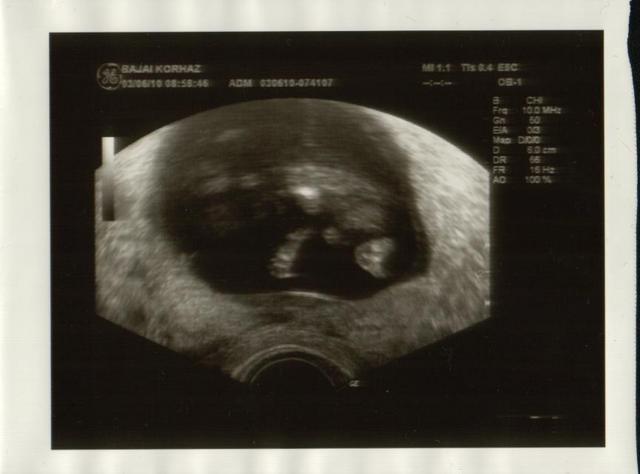

Édes kisbabám

Édes kisbabám